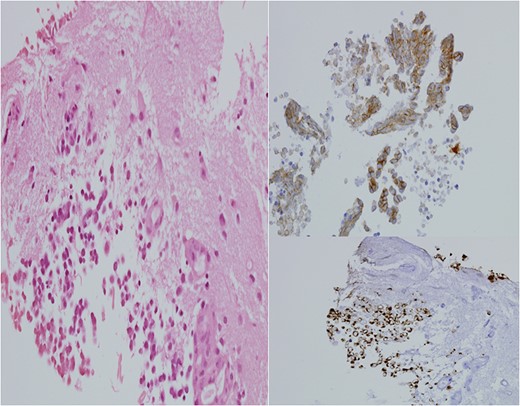

He made an uneventful recovery but presented 1 year later with intermittent dysphasia and confusion. MRI of the brain revealed a homogeneously enhancing lesion in the left posterior temporal lobe (Fig. 1). Staging CT scans identified no other lesions and this was felt to be an isolated metastasis. The patient had a craniotomy and excision of the tumour. Histopathology confirmed a high-grade neuroendocrine carcinoma with an identical immunohistochemical profile consistent with metastatic Merkel cell carcinoma (Fig. 2).

H&E stain for brain tissue, left. Immuno-stain for CK20, bottom right. Immuno-stain for CD56, upper right. ×400 magnification.